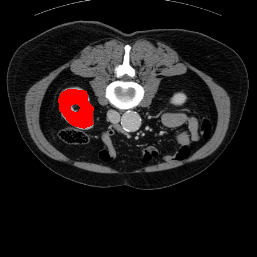

In order to assess the performance of the proposed method, we compare the performance of the proposed model with excellent models in recent years. Table 1 and Table 2 shows the comparison results of different models in setting1, while Table 3 and Table 4 shows the comparison results of different models in setting2 on the data set in recent years. PANet[25] is the most widely influential few-shot model in the field of few-shot image segmentation on natural images. SENet [18] is the first few-shot segmentation model proposed for medical images. SSL-ALPNet[19] introduced the milestone of using superpixel self-supervision to train few-shot medical image models. RPNet[29] is a supervised method with a recursive mask optimization module to iteratively optimize the segmentation mask, [27] adapt it into the same self-supervision learning framework and applies setting1 to it and denoted as SSL-RPNet; CRAPNet[27] is the latest SOTA model for 2023. Compared with CRAPNet, our method outperforms most of the state-of-the-art models and only slightly outperforms CRAPNet. Figures 3 and 4 show examples of the model’s segmentation predictions on different datasets, respectively; The first row is the support map, the second row is the label map, and the third row is the segmentation prediction of the model.